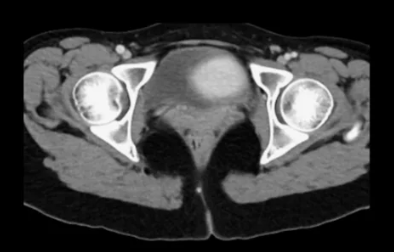

✔ 2. 영상 검사 (CT & MRI)

→ 부신 종양의 크기 및 전이 여부 확인